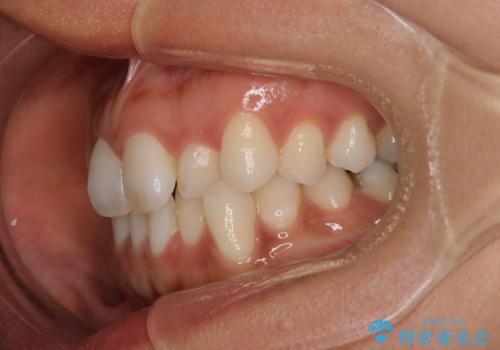

【インビザライン】前歯をきれいな歯並びにしたい

- 前歯の叢生を主訴に来院されました。このケースは抜歯をせずにIPRにてスペースを確保し、並べる計画をたてました。

きちんと使用時間を守って使用していただいたことで短い期間で治療が終了しました。